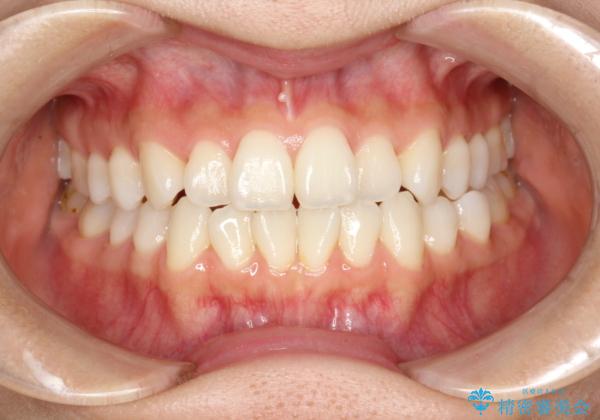

軽度の前歯のガタガタをインビザラインでの目立たない矯正

- 前歯のガタガタを主訴に来院されました。

軽度であったため、枚数制限のあるタイプのインビザラインのプランで治療することとしました。

軽度のガタガタを目立たずに手軽に矯正できるのもマウスピース矯正の魅力といえます。